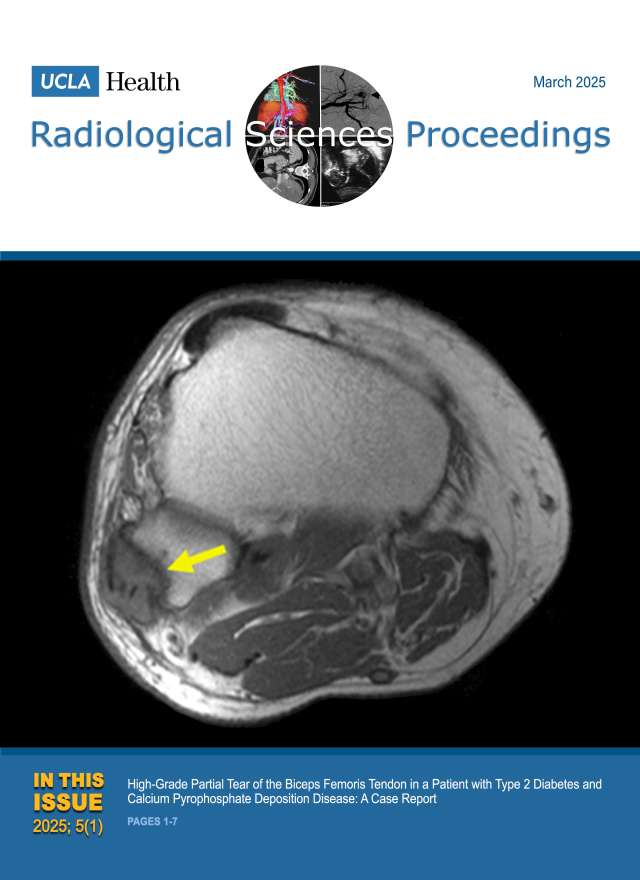

December 2024

Volume 4, Issue 4

- Smoking-Related Interstitial Lung Disease: CT Image-Based Review and Update

- Postcholecystectomy Syndrome due to Prominent Remnant of the Cystic Duct and Choledocholithiasis: A Case Report

- Kommerell Diverticulum and Agenesis of the Left Common Carotid Artery in a Patient with Dysphagia: A Case Report

- Extensive Subcutaneous Calcinosis and Hypercalcemia in the Setting of Mineral Oil-Injection-Related Foreign Body Reaction: A Case Report